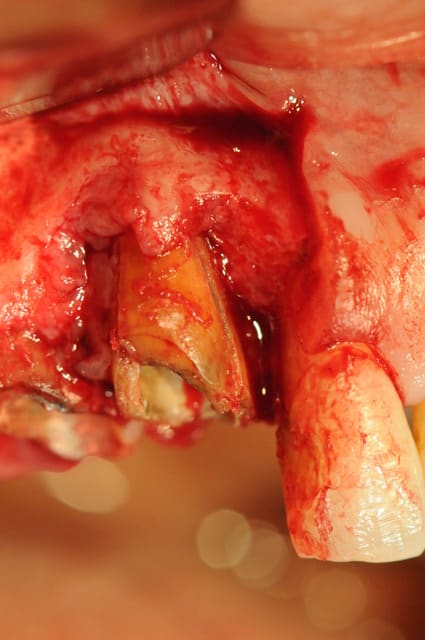

Patiente présente une perte alvéolaire de la table externe suite à fracture radiculaire.

Lambeau lev  qrpmt7 - Eugenol

Alv ole nettoy e fnw3s8 - Eugenol